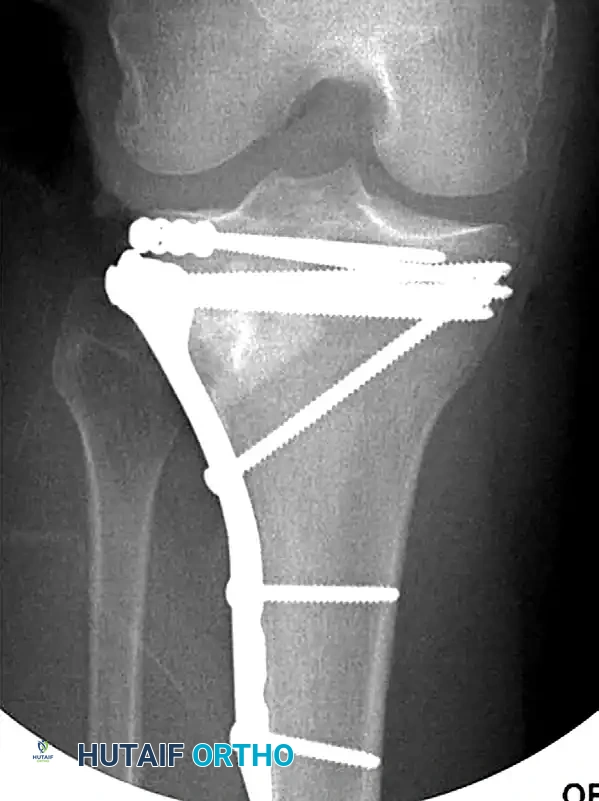

Open Reduction and Internal Fixation (ORIF)

Displaced fractures of the medial condyle (Schatzker IV) are high-energy, highly unstable injuries. They are best treated with open reduction and application of a medial buttress plate. Because the medial plateau bears approximately 60% of the knee's weight-bearing load, robust biomechanical support is mandatory.

For complex bicondylar fractures (Schatzker V and VI), traditional extensile exposures (e.g., Mercedes-Benz incisions or massive single midline incisions with extensive stripping) have historically resulted in catastrophic soft tissue complications, including flap necrosis and deep osteomyelitis.

Modern techniques emphasize minimally invasive plate osteosynthesis (MIPO) and dual plating through separate incisions. Mills and Nork demonstrated that dual plating can be safely achieved by utilizing an anterolateral incision combined with a posteromedial incision, leaving a wide, well-vascularized soft tissue bridge. Subperiosteal dissection is strictly limited to the fracture margins and the footprint of the plate. The use of small-fragment (3.5-mm) AO/ASIF T-plates has gained favor; their lower profile and increased malleability provide excellent buttressing of osteochondral fragments with significantly less soft tissue irritation than bulky 6.5-mm L-plates.